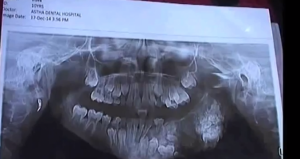

7-vuotiaalta poistettiin 80 hammasta – video!

11.02.2018

11:00